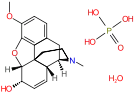

Morphinones and morphols

- 14-Cinnamoyloxycodeinone

- 14-Ethoxymetopon

- 14-Methoxymetopon

- 14-Phenylpropoxymetopon

- 3-Acetyloxymorphone

- 3,14-Diacetyloxymorphone

- 7-Spiroindanyloxymorphone

- 8,14-Dihydroxydihydromorphinone

- Acetylcodone

- Acetylmorphone

- α-hydrocodol (=dihydrocodeine, )

- Benzhydrocodone

- Bromoisopropropyldihydromorphinone cas?

- Codeinone

- Codoxime

- Conorfone (codorphone)

- IBNtxA

- Thebacon (acetyldihydrocodeinone, dihydrocodeinone enol acetate)

- Hydrocodone

- Hydromorphone

- Hydroxycodeine

- Metopon (=methyldihydromorphinone)

- Morphenol

- Morphinone

- Morphol

- N-Phenethyl-14-ethoxymetopon

- Noroxymorphone

- Oxycodone

- Oxymorphol

- Oxymorphone

- Pentamorphone

- Semorphone

Structures

| Morphinones and morphols | ||||

α-hydrocodol α-hydrocodol(Dihydrocodeine) |

Codol Codol(Codeine Phosphate) |

Hydrocodone Hydrocodone |

Hydromorphone Hydromorphone |

Hydroxycodeine Hydroxycodeine |